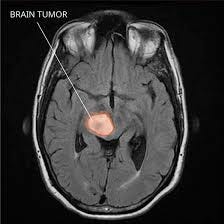

A brain tumor is an abnormal growth of cells within the brain or its surrounding tissues. Tumors can be either benign (non-cancerous) or malignant (cancerous), and they can arise from various types of cells in the brain. These growths can interfere with normal brain functions and lead to a range of symptoms, depending on their size, location, and type. Treatment options for brain tumors include surgery, radiation therapy, chemotherapy, and targeted therapies, which are chosen based on the tumor’s characteristics and the patient’s overall health.